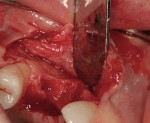

After oral sedation with 0.25 mg triazolam 1 hour prior to surgery and local anesthetic induction using 2% lidocaine with 1:100,000 epinephrine and 0.5% bupivacaine with 1:200,000 epinephrine, a palatally oriented horizontal incision was made in the edentulous No. 6 ridge with a sulcular extension to the mesio-buccal aspect of tooth No. 7 and disto-buccal aspect of tooth No. 5. To increase visualization, a vertical incision with a small right angle coronal modification was placed at the disto-buccal line angle of No. 5; a straight vertical cut followed at the mesio-buccal line angle of No. 7. A full-thickness flap was elevated past the mucogingival junction, and periodontal scoring took place near the base of the flap to facilitate the coronal advancement necessary for primary closure. Degranulation of the residual ridge using a pear-shaped carbide finishing bur and Prichard curette proceeded. Mild vertical and horizontal defects (≤ 3 mm) were detected (Figure 5 and Figure 6).